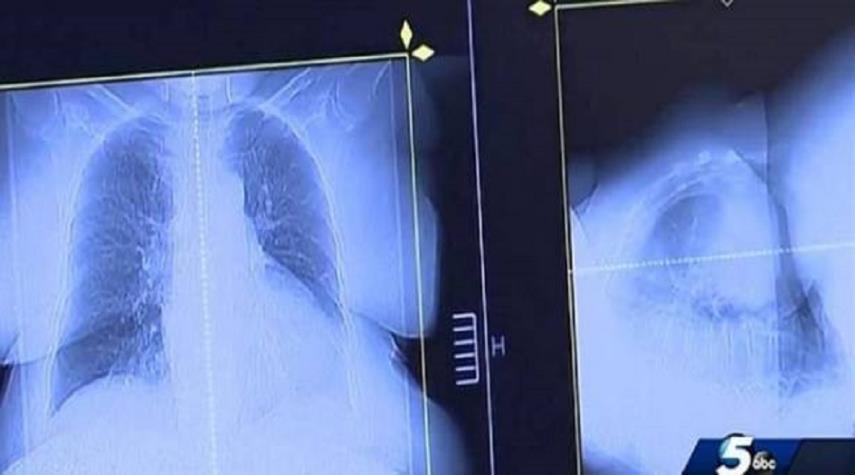

توقع الأطباء وفاته في غضون 3 أشهر.. فعالج نفسه من السرطان بدواء للكلاب!!

منوعات_الكوثر: في قصة غريبة، لجأ أميركي إلى علاج غير تقليدي، ساعده على الشفاء من السرطان، بفضل عقار يستخدم عادة لعلاج الكلاب.